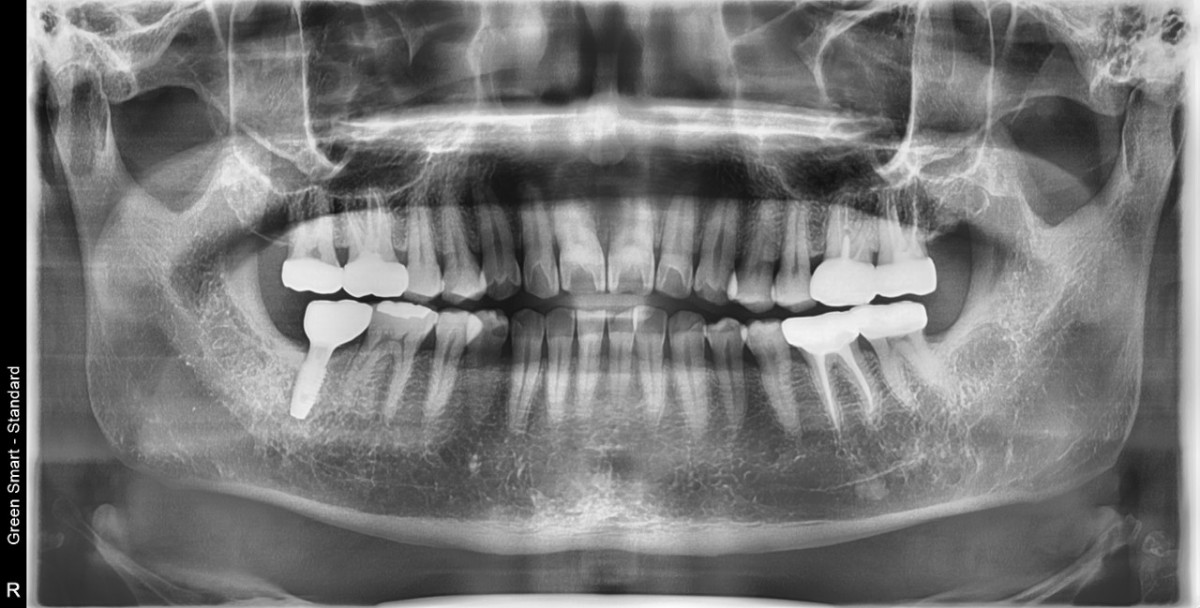

Single implant (staged) Arum NB1, f/u

A 47-year-old male patient had a crown with an ill-fitting margin and crack-tooth syndrome in the lower 2nd molar. No systemic issue.